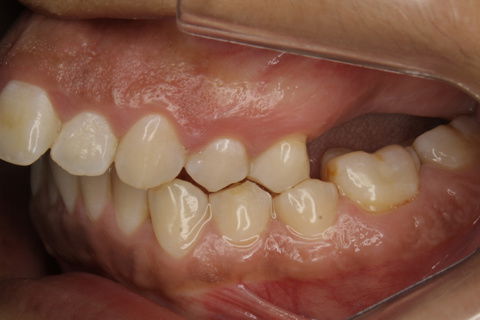

Foto Inicial.